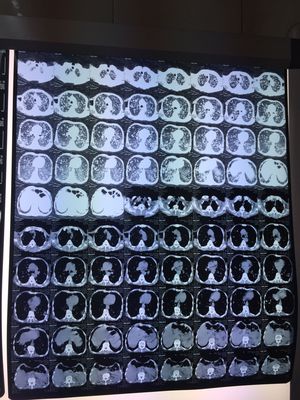

肺转移性Ca

Cancer

Lung